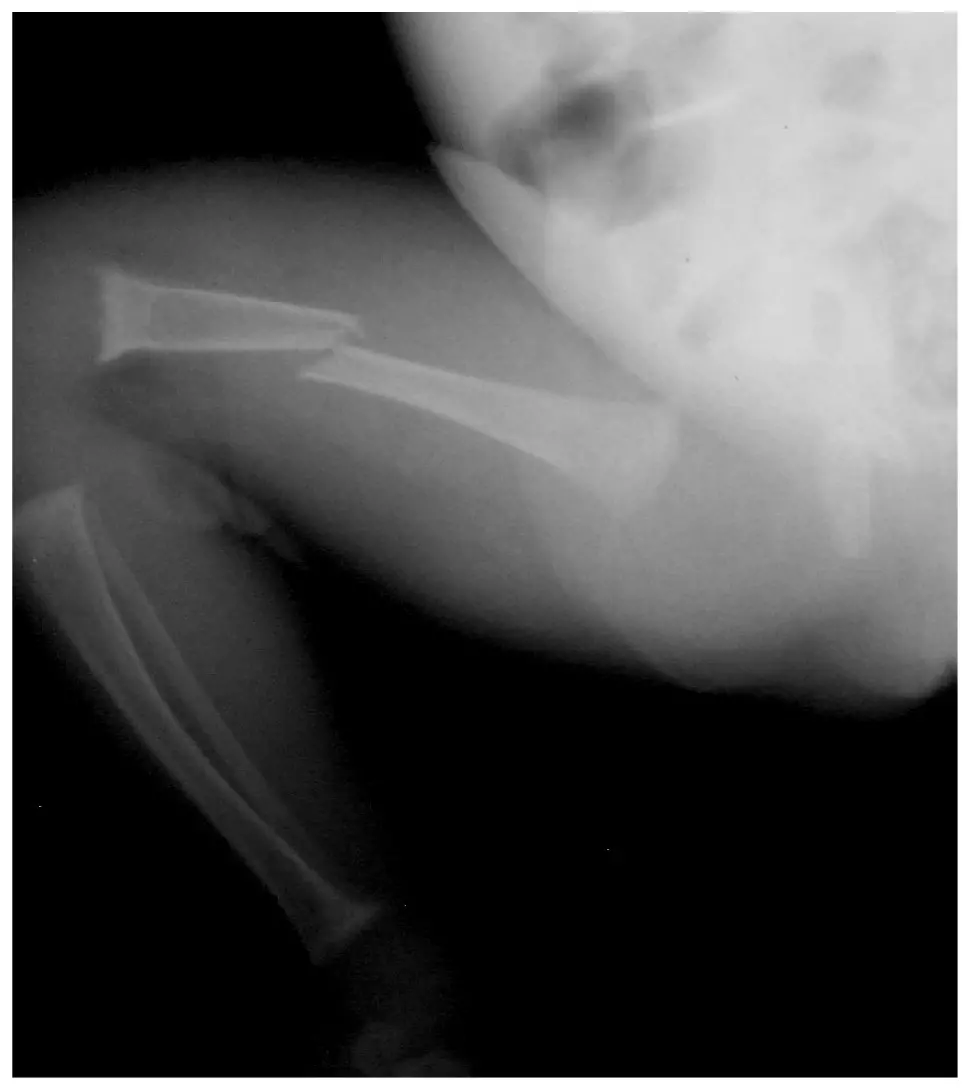

3,5-miesięczny wcześniak urodzony w 32. Hbd, z masą ciała 700 g, z obciążonym okresem noworodkowym (długotrwała mechaniczna wentylacja, BPD, długotrwałe żywienie pozajelitowe, cholestaza, nietolerancja karmienia) został przyjęty do naszej kliniki z powodu podejrzenia ciężkiej postaci krzywicy. Dziecko karmione Bebilon pepti MCT, otrzymywało 1500 IU/d witaminy D. Dwa tygodnie przed przyjęciem do kliniki doszło do obustronnego złamania trzonów kości udowych (w odstępie kilku dni) oraz złamania trzonu lewej kości ramiennej (ryc. 1, ryc. 2). W rejonie rozpoznano krzywicę z niedoboru witaminy D i włączono do leczenia witaminę D,

początkowo w dawce 10 000 IU/d (następnie 4000 IU/d), i przekazano dziecko do dalszej diagnostyki do IPCZD. Przy przyjęciu do naszej kliniki w badaniu przedmiotowym zwracały uwagę cechy wcześniactwa, cholestatyczne zabarwienie powłok skórnych, duża głowa z wydatnymi guzami czołowymi, duże ciemiączko (3 × 4 cm), majtki gipsowe na kończynach dolnych oraz opatrunek Desaulta na lewej kończynie górnej. Na podstawie wykonanych badań (tab. 7) postawiono u dziecka rozpoznanie osteopenii wcześniaczej związanej z niedoborem fosforanów. Oddalono podejrzenie krzywicy niedoborowej. W leczeniu zastosowano dietę bogatą w Ca i P (mleko dla wcześniaków) oraz prowadzono suplementację fosforanami drogą doustną. Z powodu hiperkalciurii odstawiono podaż witaminy D do czasu normalizacji wydalania Ca z moczem. Następnie włączono preparat 25-hydroksywitaminy i stosowano do czasu ustąpienia cholestazy. W trakcie suplementacji fosforanami obserwowano tendencję do niższych wartości Ca we krwi, co potwierdzało, iż u dziecka mamy nie tylko niedobory ustrojowe fosforanów, ale również wapnia. Do leczenia dołączono suplementację wapniem. Pozwoliło to na normalizację parametrów biochemicznych gospodarki Ca-P. Obserwowano również zrost kości długich, choć ze skróceniem kości udowych (przemieszczenie odłamów) (ryc. 3, 4).

Ryc. 2. Złamanie trzonu kości ramiennej – widoczny zrost

Ryc. 4. Złamanie trzonów kości udowych – widoczny zrost ze skróceniem kończyn (L > P)